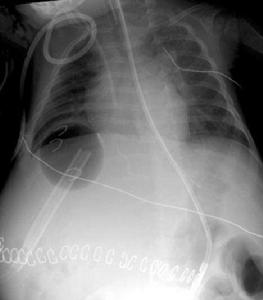

2.X線鋇餐造影是臨床首選X線檢查方法,具有方便、安全、無創傷性。可顯示主動脈弓以下食管黏膜呈蟲蝕樣或串珠樣充盈缺損,在食管蠕動時上述現象消失,以區別食管癌。對疑似病人,檢查時作Valsalva動作或注射654-2可提高檢出率。

3.計算機斷層掃描(CT)CT掃描對肝內性及肝外性門靜脈高壓的診斷均有十分重要的意義。CT掃描不僅可清晰顯示肝臟的外形及其輪廓變化,還顯示實質及肝內血管變化,並可準確測定肝臟容積。Tones等研究證實,肝硬化時右葉體積縮小15.2%,左葉中段沒有明顯變化,側段增大55.6%,尾葉增加19.2%。CT掃描圖像可明確提示門靜脈系有無擴張及各側支血管的形態變化,注入造影劑之後可顯示有無離肝血流。CT掃描可精確測定脾臟容積,明確腹水、門靜脈及其屬支內有無血栓或瘤。對臍靜脈和腹膜後靜脈曲張的檢出率(97%、100%)高於靜脈造影(17%、30%)。並能發現布-卡氏綜合徵患者肝靜脈或下腔靜脈狹窄或閉縮的程度、部位等。